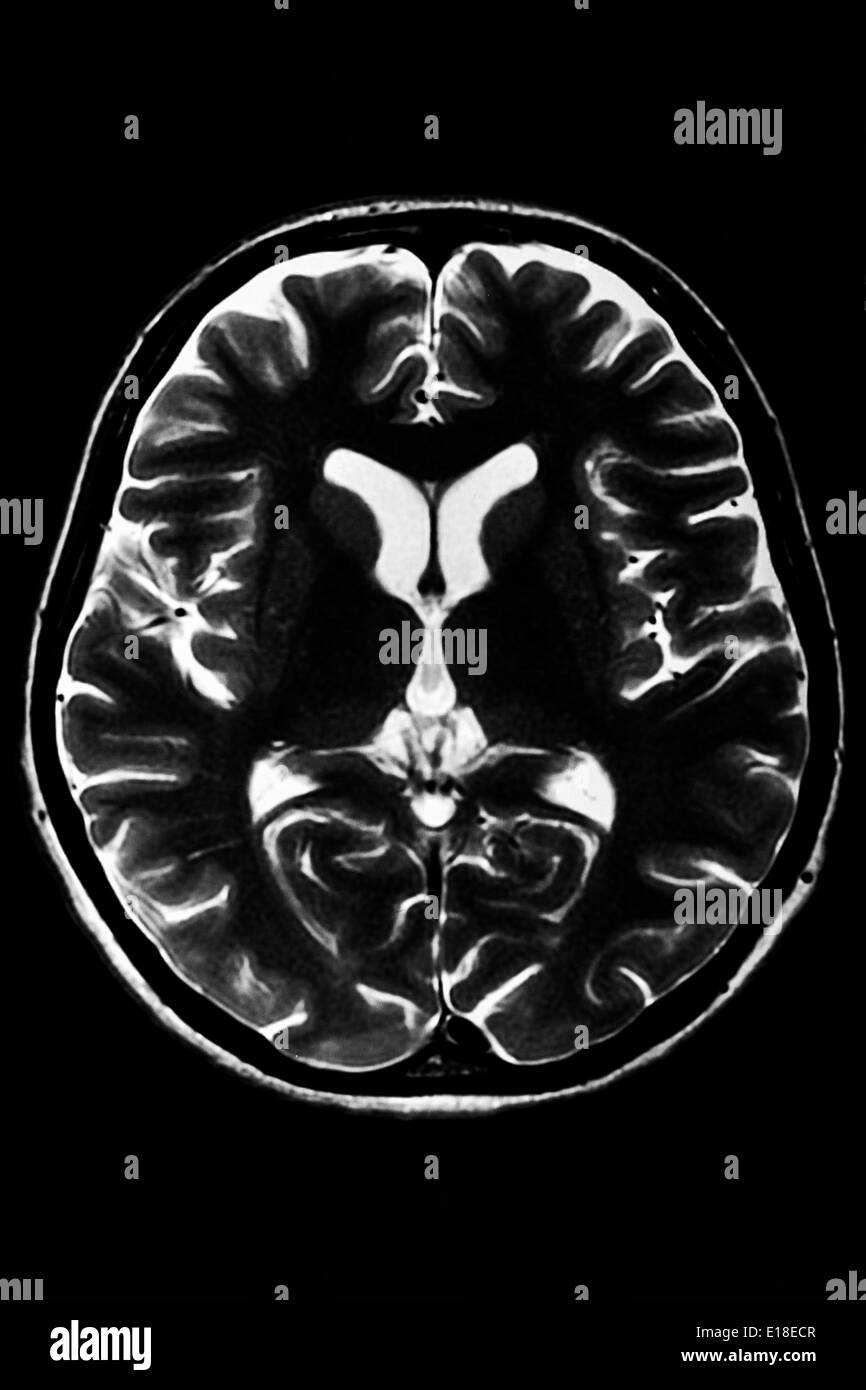

La section horizontale d'un cerveau humain - IRM Banque D'Imageshttps://www.alamyimages.fr/image-license-details/?v=1https://www.alamyimages.fr/la-section-horizontale-d-un-cerveau-humain-irm-image69643079.html

La section horizontale d'un cerveau humain - IRM Banque D'Imageshttps://www.alamyimages.fr/image-license-details/?v=1https://www.alamyimages.fr/la-section-horizontale-d-un-cerveau-humain-irm-image69643079.htmlRFE18ECR–La section horizontale d'un cerveau humain - IRM